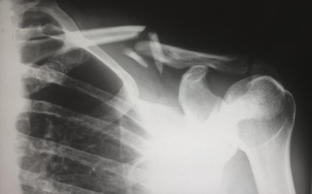

X-ray of a broken shoulder

Finding the best treatment for orthopedic pain, injury, or disease starts with an accurate diagnosis. Based on our initial findings, our professional staff may decide upon a series of specialized diagnostic tests. Our Southeastern Orthopaedic Specialists, P.A. divisions use advanced orthopedic imaging tools to create precise and detailed images of damaged bones, joints, and tissues. Our orthopaedists use the results of these tests to plan an appropriate course of treatment. Our imaging centers offers a complete spectrum of services including the most advanced equipment available: high field technology MRI, EMG for testing of muscles and nerves, and radiographic (x-ray) and fluoroscopic equipment.